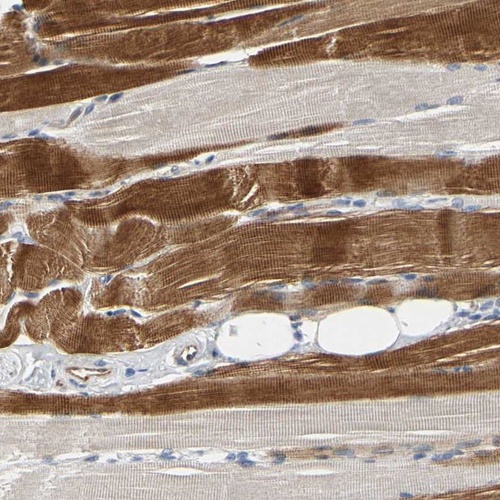

Immunohistochemical staining of human skeletal muscle shows moderate cytoplasmic positivity in myocytes.